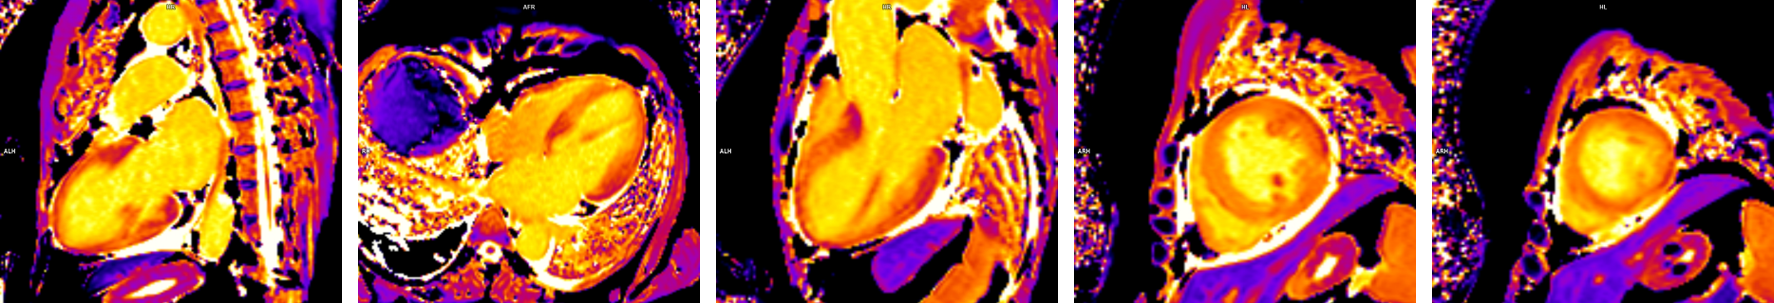

Figura 1: Achizitie harta T1 (T1 mapping) precontrast

Figura 2: Achizitie harta T2 (T2 mapping)

Figura 3: Achizitie harta T1 (T1 mapping) postcontrast

Figura 4: Secventa de edem (achizitie T2 cu saturatia grasimii)

Figura 5: Postcontrast achizitie tripla inversie-recuperare in ax scurt

Examinarea IRM evidențiază formă tipică a ventriculului stâng care e balonizat, cu edem miocardic de la nivelul cavitații medii până la apex (examinarea cardiacă prin rezonanță magnetică este singura modalitate de a evidenția „in vivo” edemul miocardic) și, în mod caracteristic, fără priză de contrast ceea ce sugerează lipsa ariilor de necroză miocardică.